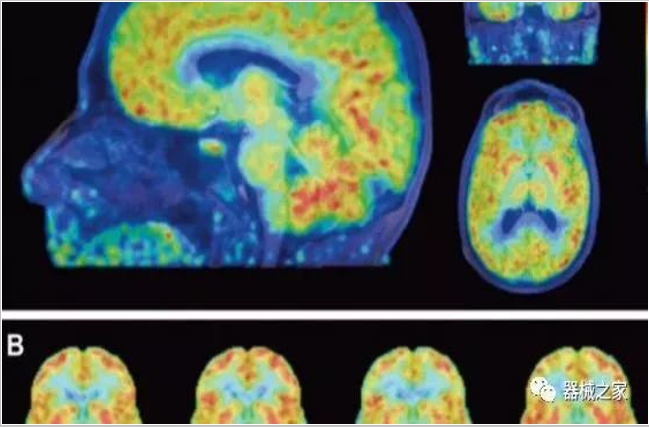

PET/CT探測(cè)器的發(fā)展?fàn)顩r

正電子發(fā)射型斷層儀(Positron Emission Tomography, PET)是對(duì)正電子示蹤劑的探測(cè)設(shè)備,具有極高靈敏度和精準(zhǔn)的定量功能。而PET/CT是將PET與CT有機(jī)結(jié)合起來(lái)的融合設(shè)備,已經(jīng)成為腫瘤、神經(jīng)和心血管系統(tǒng)疾病診斷,臨床分期和療效評(píng)估的最佳影像技術(shù)。

PET掃描顯示成年女性大腦比男性年輕三歲!